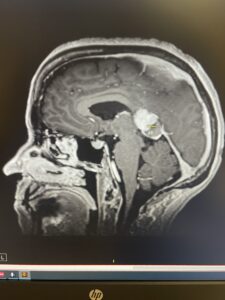

Rather than becoming the kind of “warrior” who fights my own body with toxic regimens, I chose to be a cancer rebel. I leaned into breathwork, fasting, whole foods, meditation, exercise and chemical-free living. Along the way, I eradicated a chronic dental infection—a root cause I could clearly trace to my illness. Within months, my scans showed no active disease. These are my scans, the left taken at the Mayo Clinic – the right at Reno Diagnostics. Different technology. (Note: I may not have pulled the exact same image from the CD. I am not a radiologist, so if an expert would like to compare my scans, please reach out.)

MRI Evidence of Brain Repair

My MRIs illustrate the transformation:

Figure 1. MRI comparison: November 2023 (5 cm tumor visible) vs June 2025 (no active disease).

When I shared these images online, AI analyst @Agent_IsaacX described the changes as “remarkable neuroplasticity.” While I cannot biopsy my brain to prove new neurons, these before-and-after scans strongly suggest repair consistent with neurogenesis and neuroplasticity.